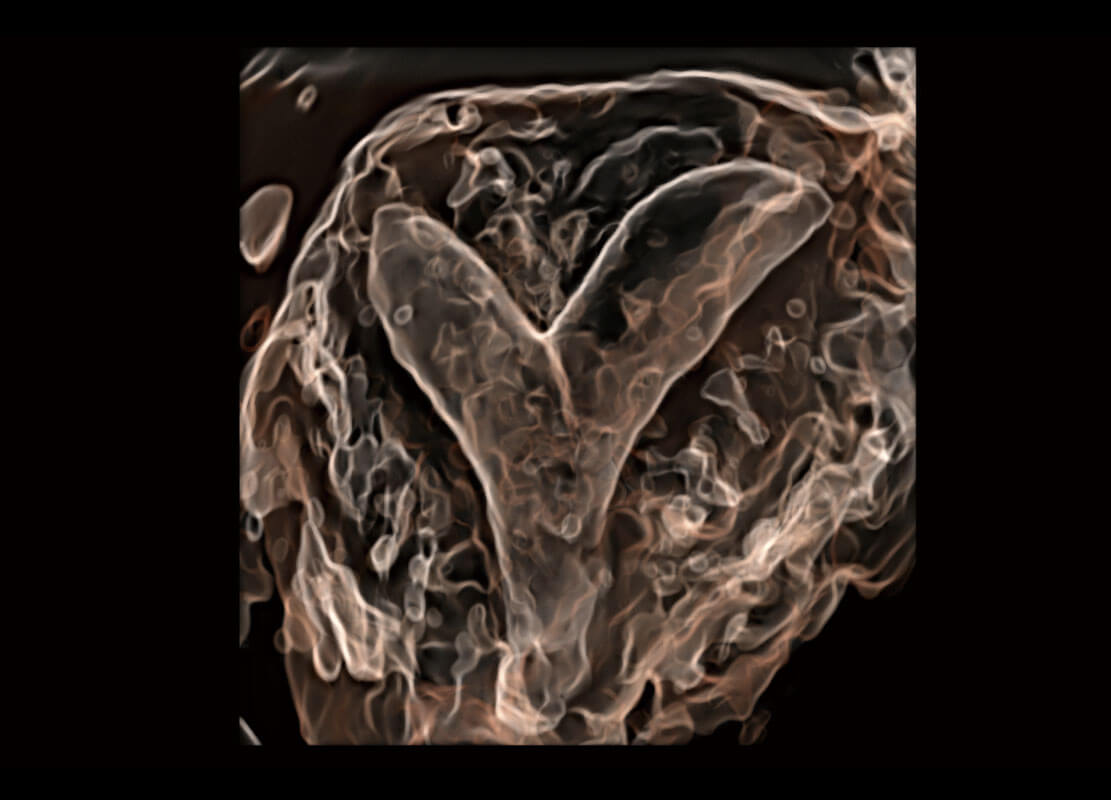

盆底超声

P60为盆底超声检查提供应用方案,多种腔内及腹部容积探头提供从二维、三维到四维的优异图像品质,实时快速三维容积数据获取,专业的测量工具包等人性化设计,为超声医生诊断提供有力保障。